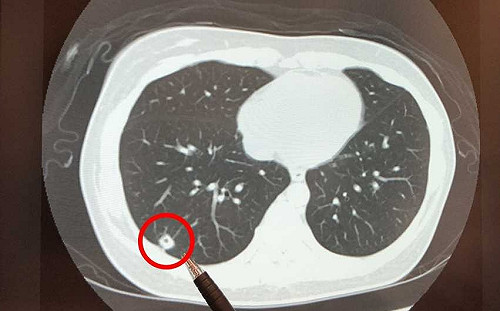

嚇壞14億人! 打科興新冠疫苗後出現肺結節?中國緊急「闢謠」